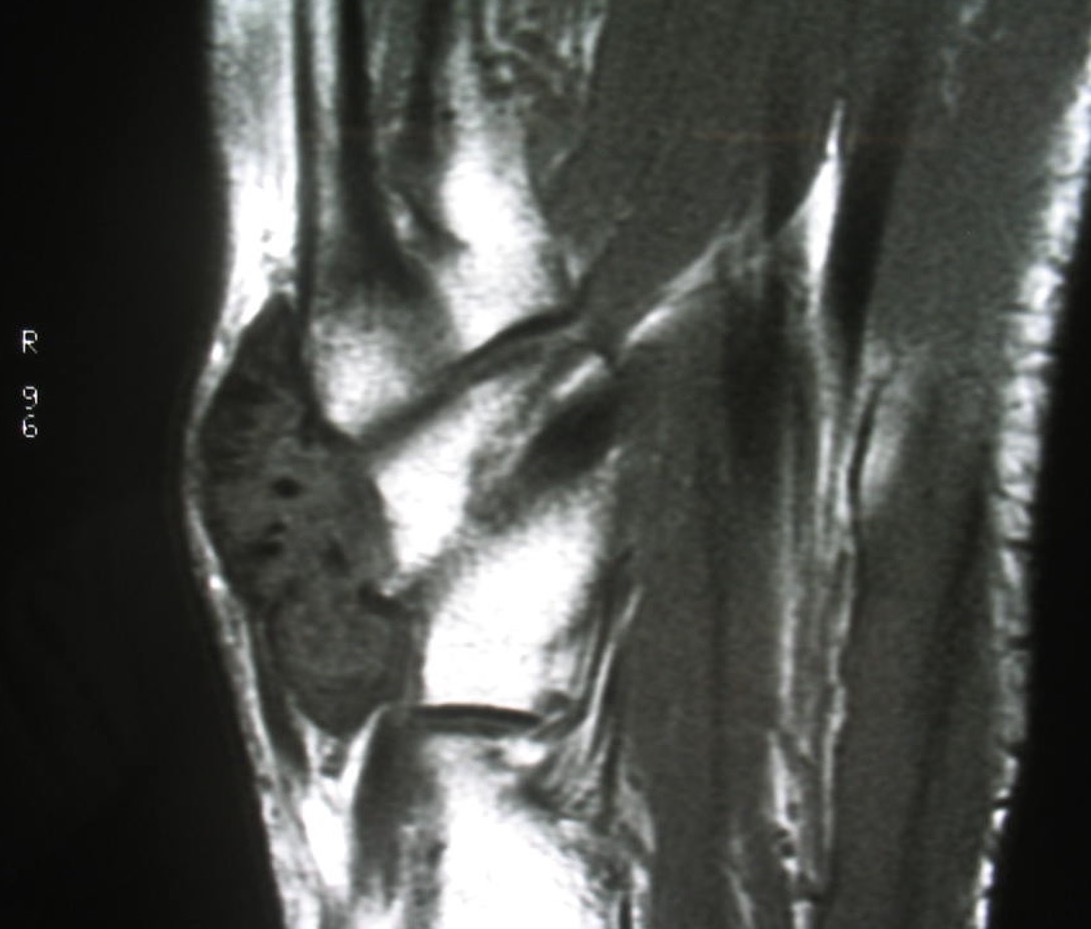

GCT flexor tendon sheath

GCT of tibialis posterior tendon sheath